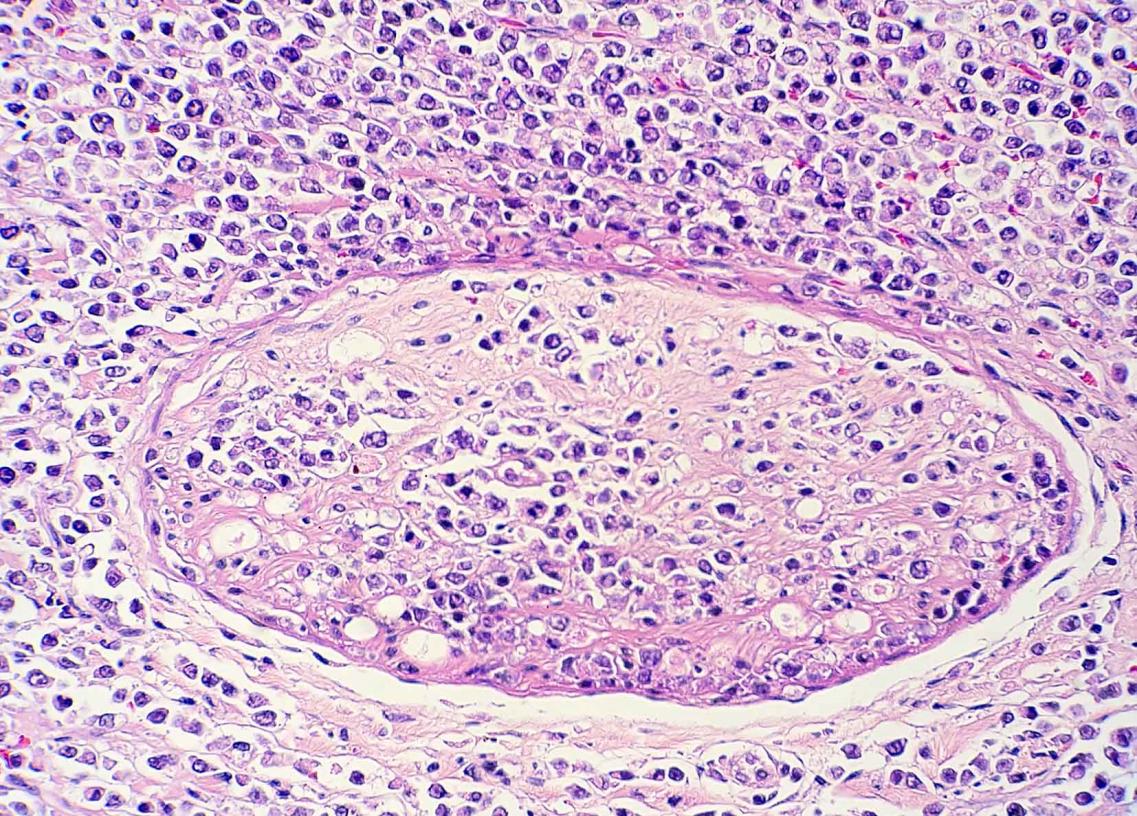

Este estudio, publicado en Transboundary and Emerging Diseases (2020; doi:10.1111/tbed.13713), ilustra el papel de la patología como herramienta de apoyo a los programas de conservación para especies en peligro de extinción. En este caso, la detección de dos herpesvirus presumiblemente nuevos en visones europeos se realizó a raíz del diagnóstico de un caso de linfoma principalmente neural/perineural con cuerpos de inclusión característicos de herpesvirus intralesionales en un visón europeo procedente del programa de cría en cautividad de esta especie amenazada. Estos virus podrían tener una influencia en el desarrollo de ésta y otras enfermedades que afectan a esta especie en cautividad y, por lo tanto, afectar a sus poblaciones.